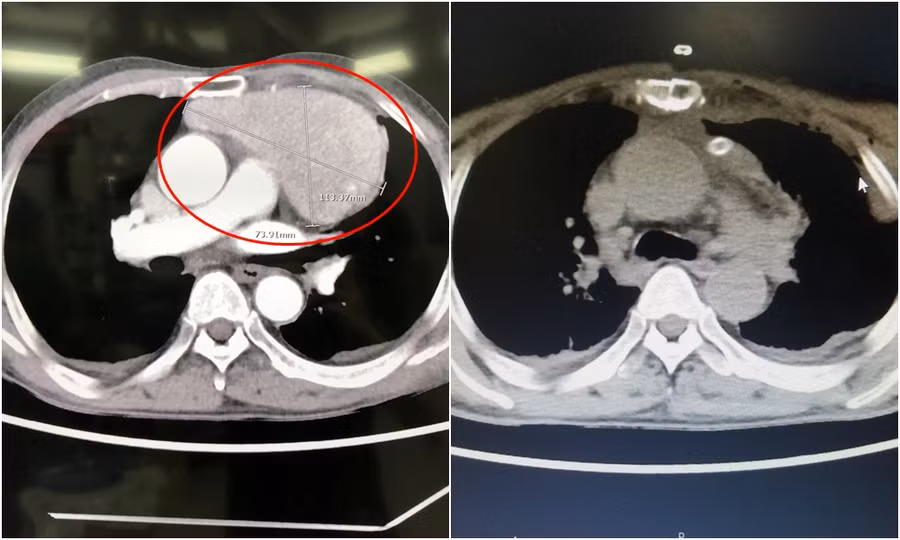

Sau khi thăm khám, các bác sĩ cho biết, khối u nằm ngay vùng trước tim, kích thước lớn bằng quả tim bệnh nhân, đè đẩy các mạch máu, tim và khí phế quản.

Các bác sĩ tiến hành phẫu thuật theo đường mở xương ức và ngực trái, lộ khối u trung thất lớn kích thước 11x7x7cm nằm đè lên tim và ép các mạch máu về tim, u tăng sinh nhiều mạch lớn dính vào các tổ chức xung quanh.